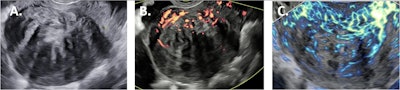

Sagittal fibroid images obtained by the different ultrasound techniques. 2D B-mode ultrasound (A); 2D power Doppler (B); 2D microvascular flow (C).All images courtesy of Derk Jan Slotman et al and Insights Into Imaging. Available for republishing under Creative Commons license (CC BY-NC-ND 4.0).